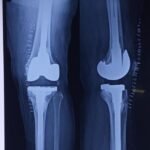

Revision knee replacement surgery is performed when a previously replaced knee joint develops problems such as pain, instability, stiffness, infection, implant loosening, or wear over time.

In this procedure, part or all of the existing knee implant is removed and replaced with new components to restore knee function and reduce pain.